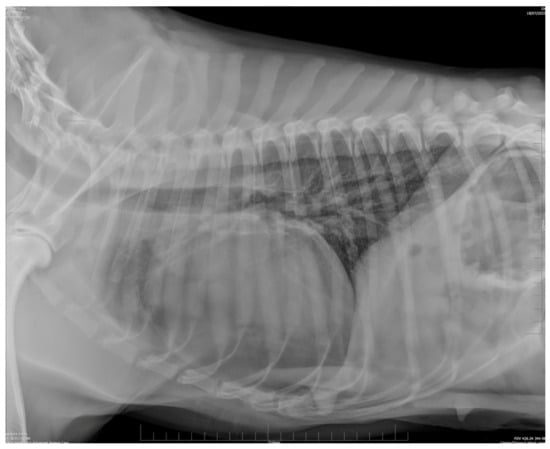

2.2. Diagnostic Imaging